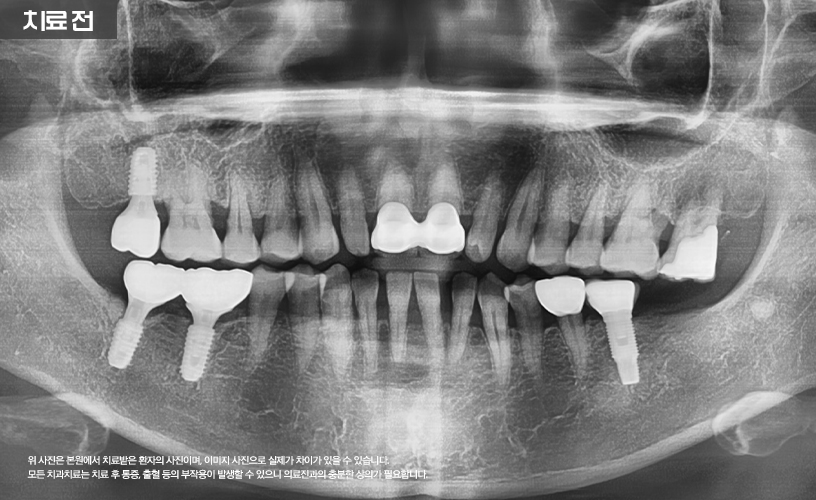

"앞니 벌어짐 3D 구강스캐너를 이용한 심미보철 치료 사례"

상기 환자분은 아랫니 치아의 공간이 매우 넓어

심미적인 스트레스로 인해 본 원에 내원하셨습니다.

앞니 사이가 벌어진 경우에는 다양한 치료

방법이 있는데 환자분께서는 레진이나 보철치료를

고려하고 오셨습니다.

환자분의 경우 앞니 사이가 많이 벌어진 상태이기

때문에 레진 치료는 어려운 상태라서

보철 치료를 고려해 볼 수 있습니다.